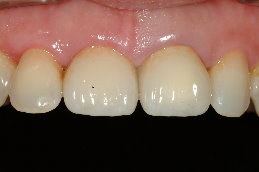

經試戴、調整、及黏著後,過了一週,病患回診所的結果:

一、正面觀(圖十),全瓷冠的外形與鄰牙自然且協調

二、前牙觀(圖十一),全瓷冠由於無金屬襯?堙A因此與牙齦相當協調。

經過全瓷冠的修復,患者得到滿意的結果,可以再度露出自信且迷人的笑容了。